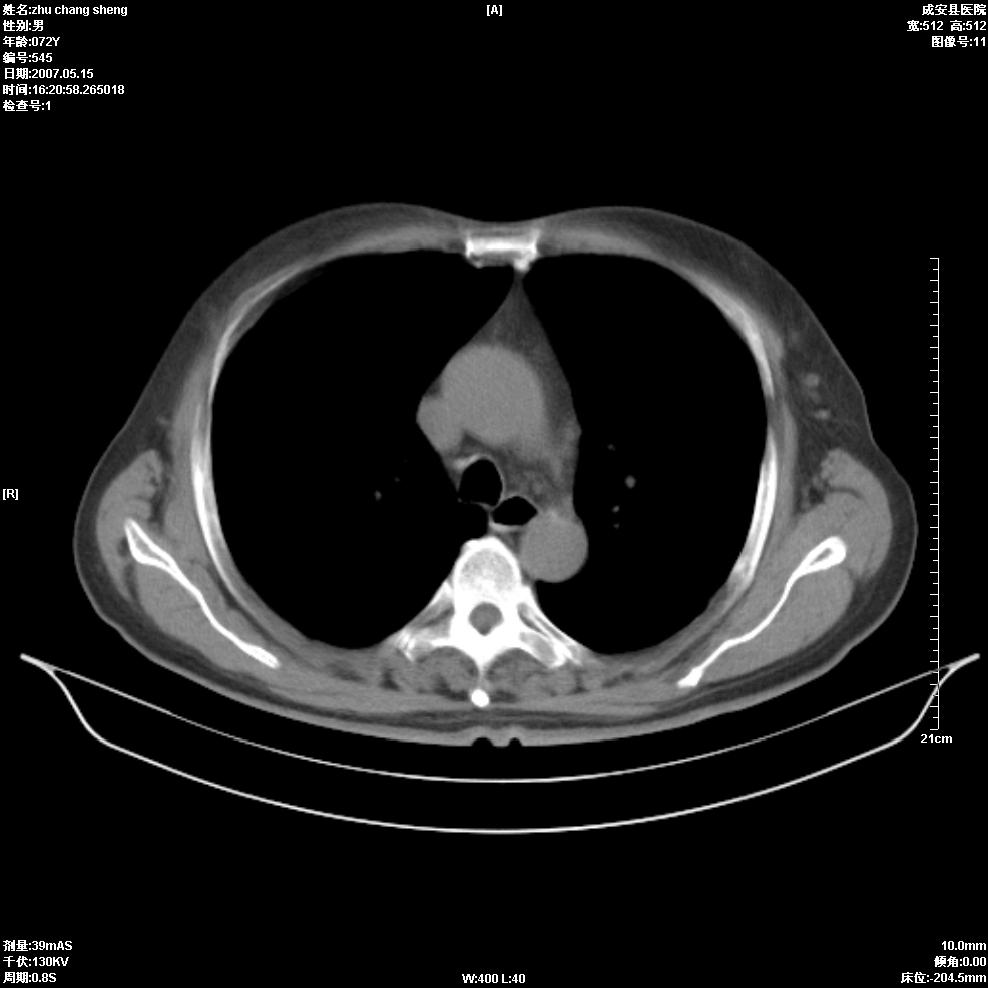

以下是引用医博云天在2007-5-15 19:10:00的发言:[br]心包积液,胸腔积液,心影增大,左心为主。

以下是引用zhangzhongshou在2007-5-15 20:21:00的发言:[br]心包积液可以肯定有,肿块显示不清,建议增强或mri检查。

以下是引用jinning在2007-5-15 21:06:00的发言:[br]心包积液可以肯定,建议增强或mri检查吧!

以下是引用拾荒者在2007-5-15 22:28:00的发言:[br]心包膜增厚,有少量积液,右室前壁示均匀软组织密度影,边界欠清,建议增强扫描或mri检查与室壁瘤鉴别。

以下是引用还珠格格在2007-5-19 9:50:00的发言:[br]病人与5月18日 做了核磁增强扫描 确诊为前上纵隔侵袭性胸腺瘤。